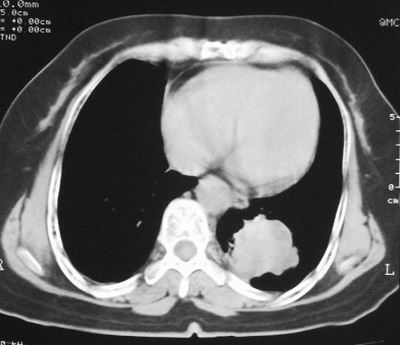

患者,女,64岁,4年前左腮腺"多形性"腺瘤手术治疗史.现复查胸部ct见左下肺块状影,该影与原左腮腺手术是否有联系?

本次复查胸部ct

左下肺软组织块影,有分叶、毛刺、空泡及胸膜牵拉征,左下肺周围性肺癌。

左肺下叶周围型肺癌,支持!(软组织肿块+分叶+毛刺+空泡+胸膜凹陷征)

左下肺软组织密度影,可见分叶,边缘可见毛刺征,胸膜增厚,强烈要求左下肺周围型肺癌

左下肺后基底段实性肿块,周围有毛刺,病变周围有肺气肿,与降主动脉间有条带状影相连,病灶4年前查体发现,纵隔内未见肿大淋巴结。考虑.肺隔离症,建议增强扫描与周围型肺癌鉴别。